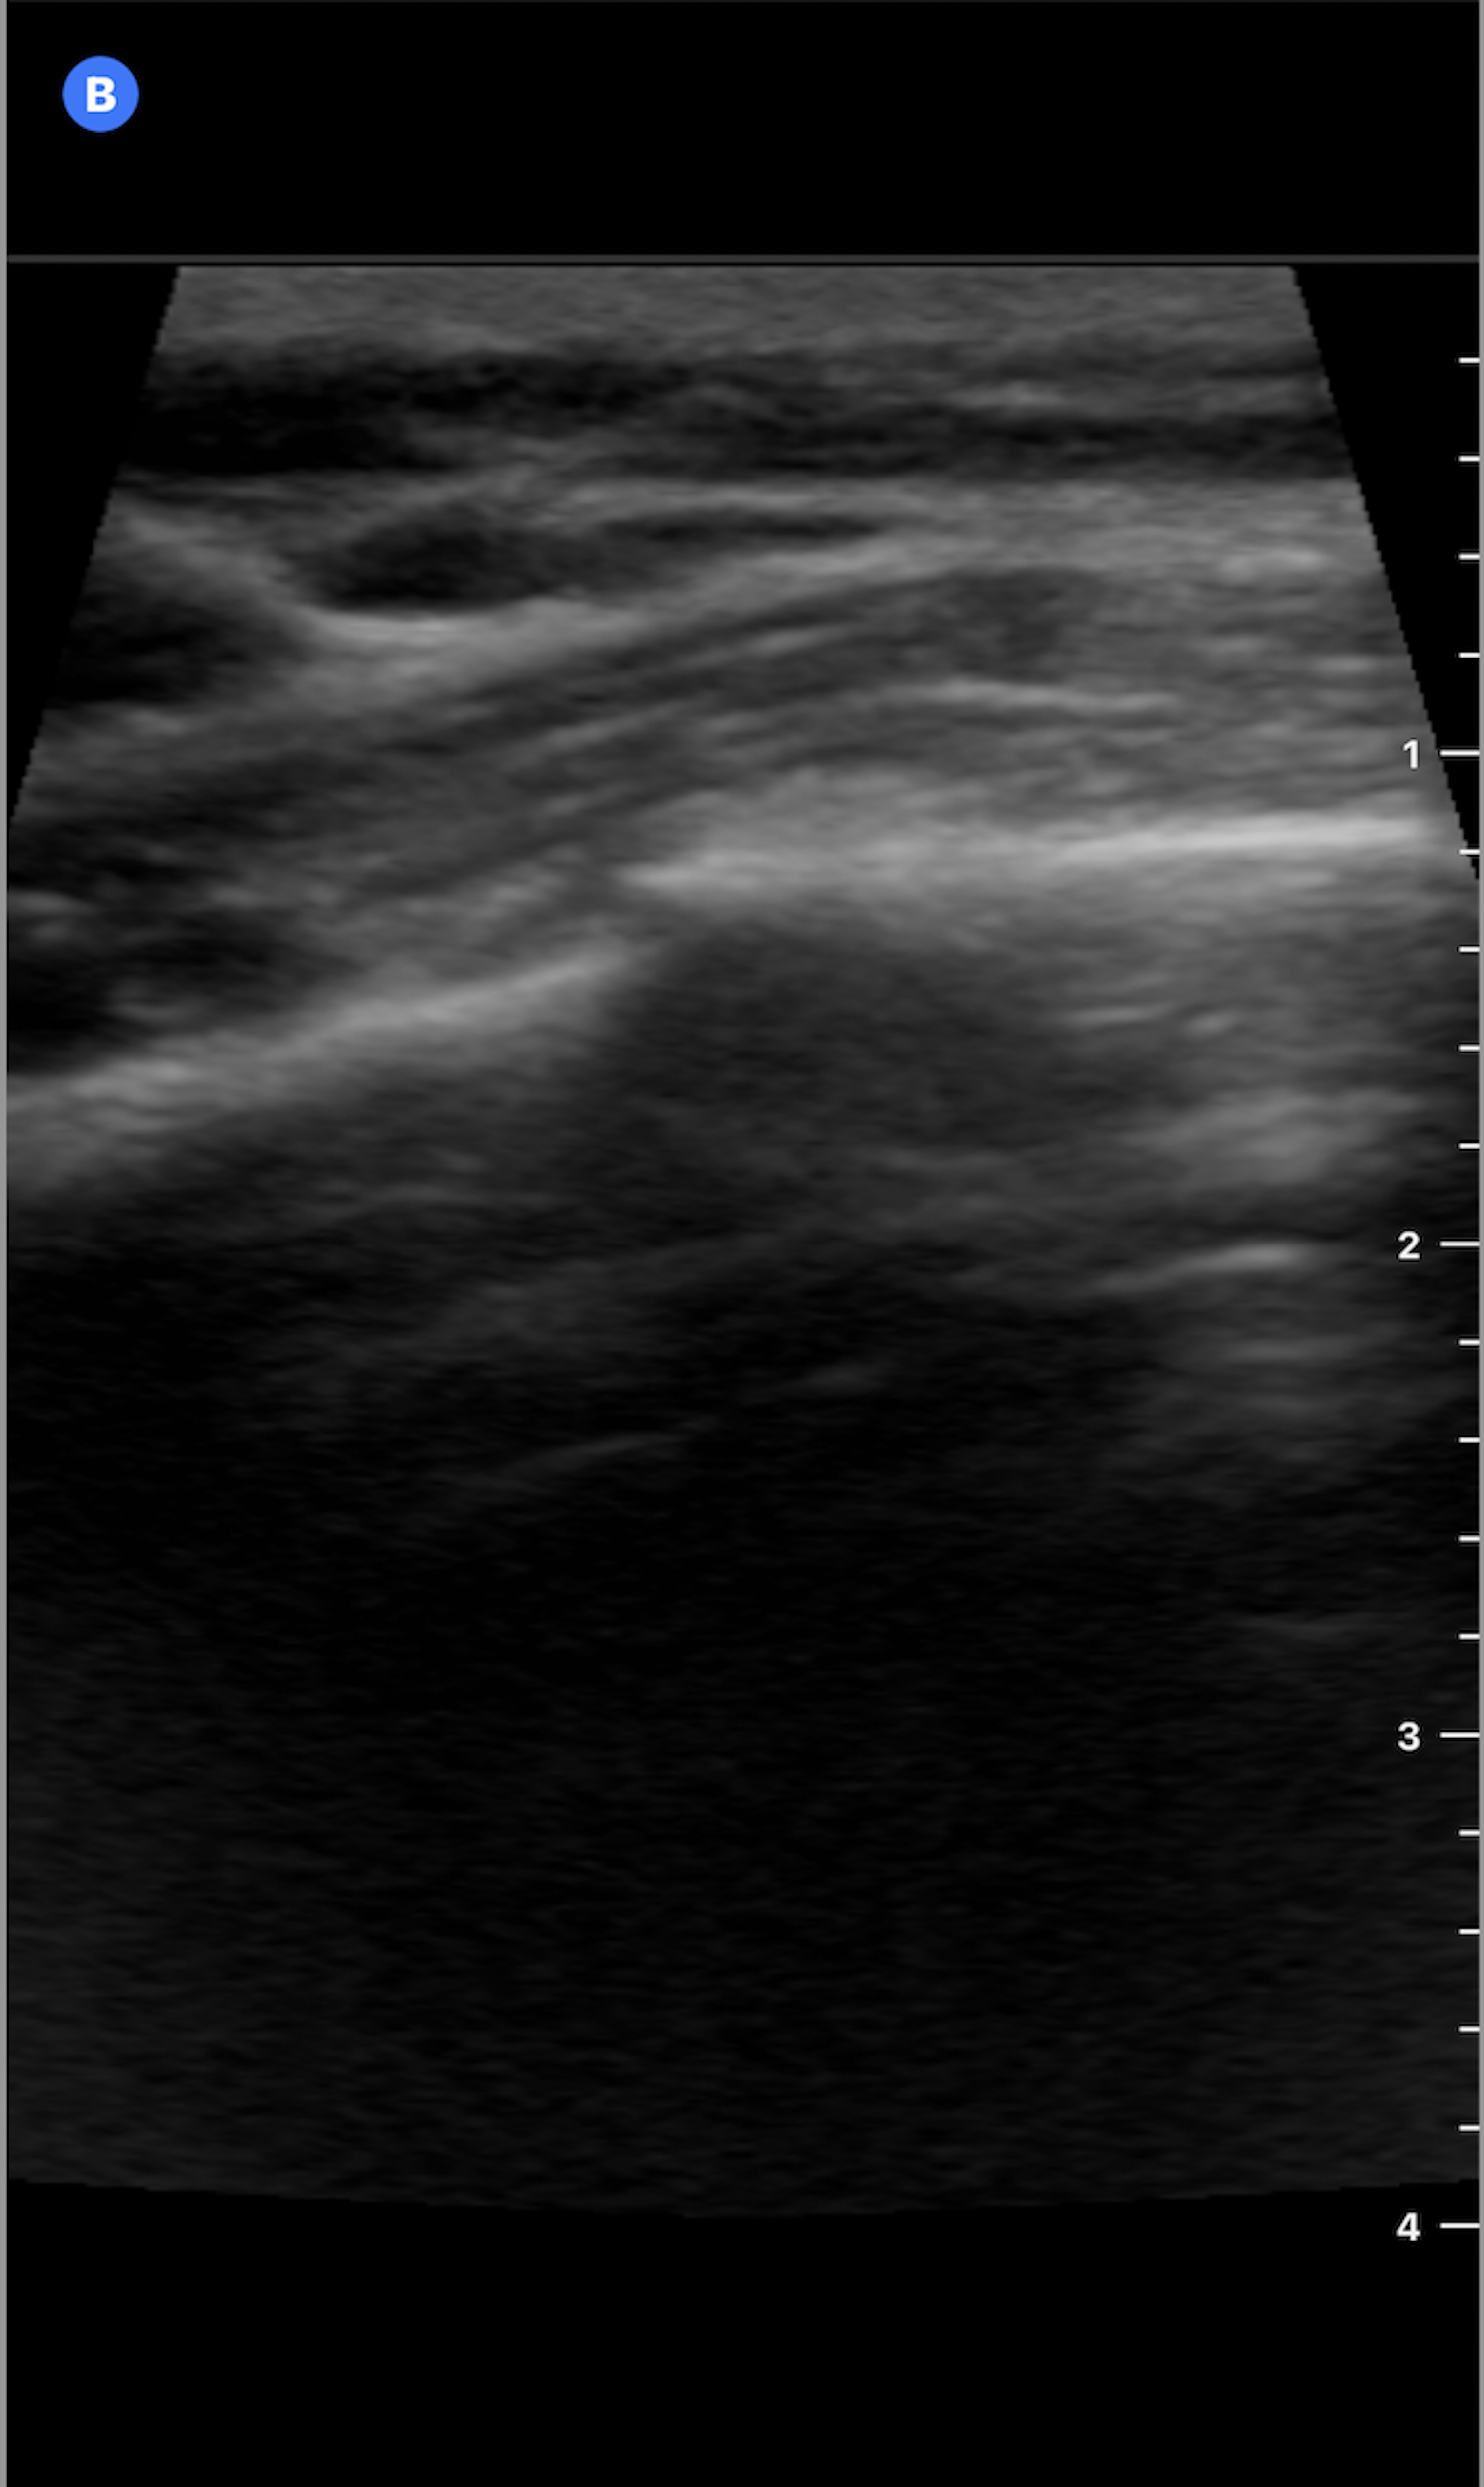

Using a high-frequency linear transducer, ultrasound evaluation of the left anterior chest wall in the longitudinal plane demonstrated disruption of the normally smooth hyperechoic rib cortex with a subtle step-off deformity. These findings were consistent with a non-displaced fracture of the fourth anterior rib.

Figure 1: Ultrasound image of the 4th anterior rib in the longitudinal plane without annotation.